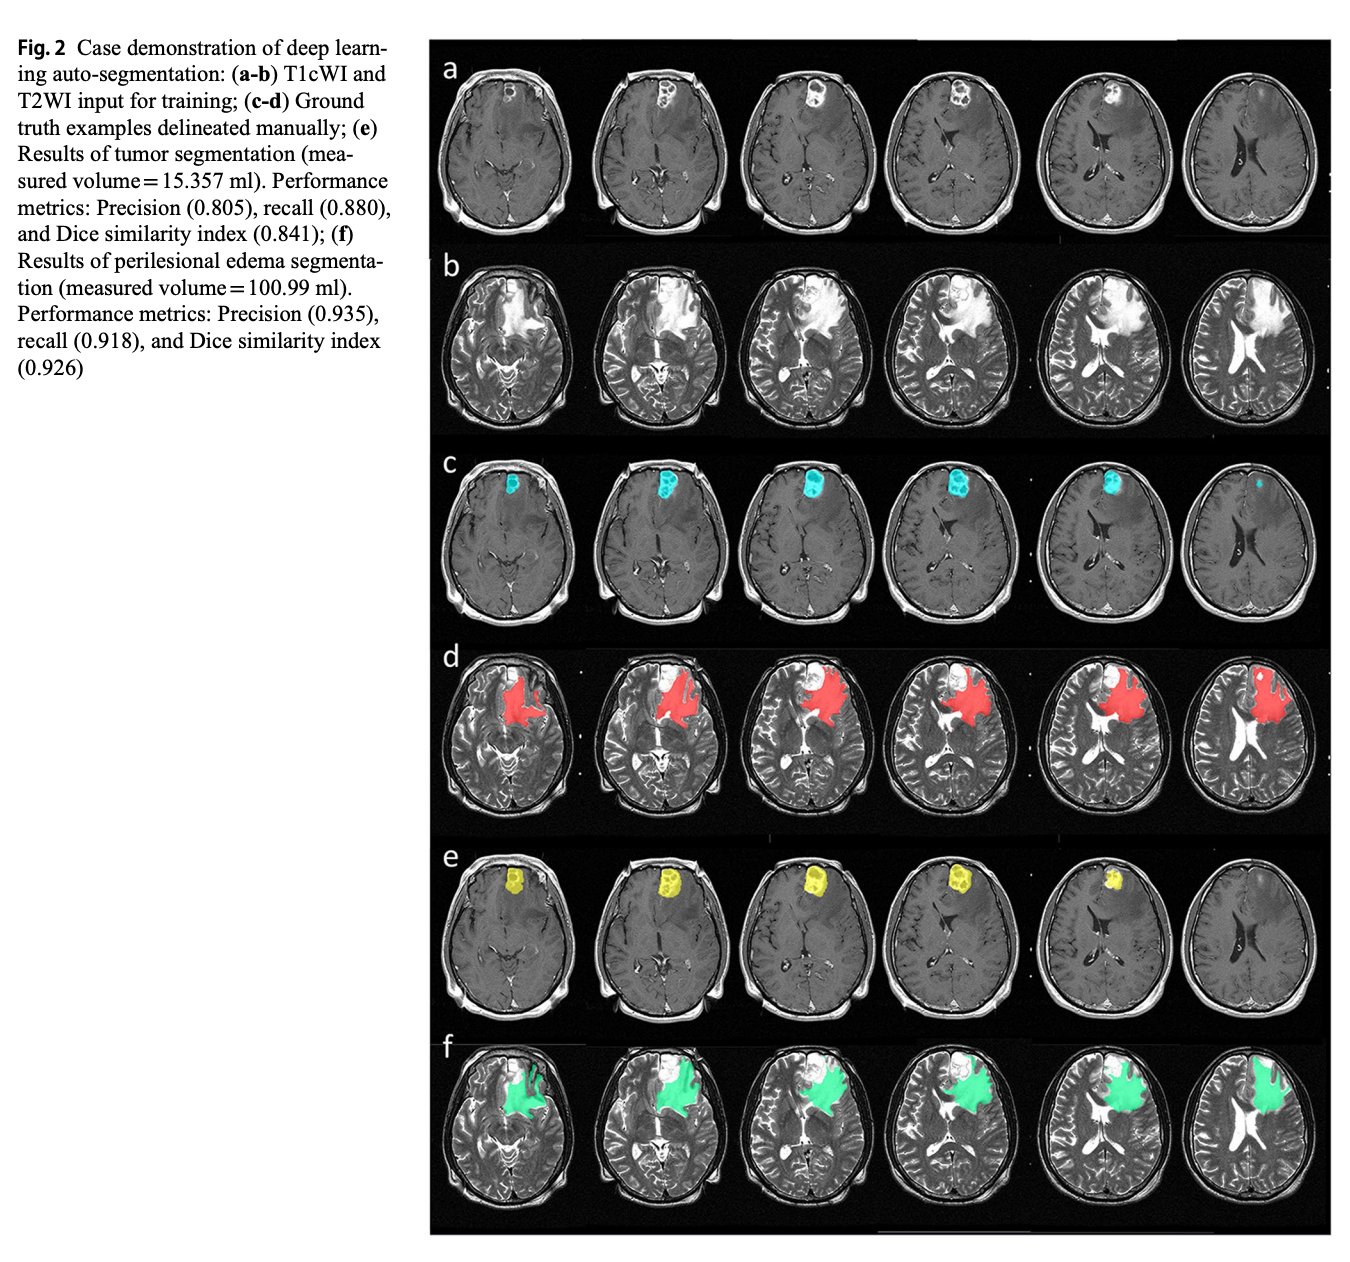

Source : www.instagram.comJournal of Neuro Oncology on X: “This recent paper by Chou et al